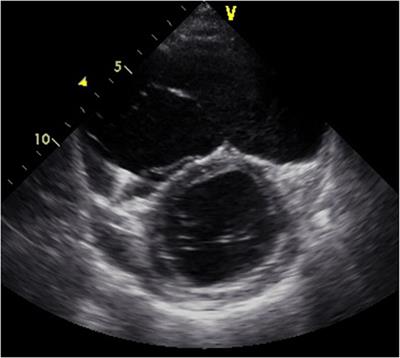

Continuous-flow left ventricular assist device treatment for arrhythmogenic right ventricular cardiomyopathy complicated by advanced biventricular failure – University of Tokyo experiences